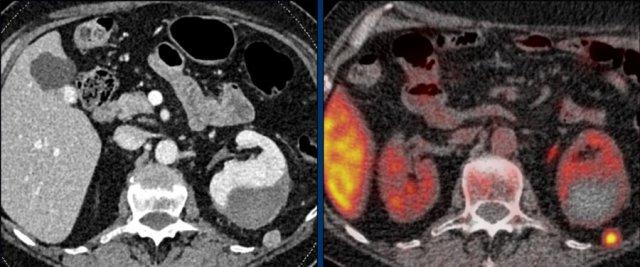

CT thì tĩnh mạch mặt cắt ngang đầu tiên sau phẫu thuật, thực hiện 3 tháng sau khi cắt tuyến thượng thận trái vì ung thư biểu mô vỏ thượng thận kích thước lớn, cho thấy một nốt ngấm thuốc ở phía sau thận trái.

PET-CT FDG tái phân giai đoạn cho thấy sự hấp thu mạnh chỉ tại tổn thương này, được xác nhận là ổ di căn trên hình ảnh theo dõi tiếp theo.

Khối máu tụ dưới bao thận trái là không liên quan.